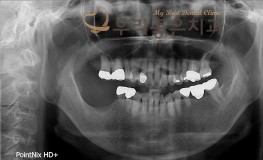

우리좋은치과 치아 상실 및 골소실 → 뼈이식 및 임플란트 보철 치료 (김** 201..

No.345

임플란트

2019-11-25

1552